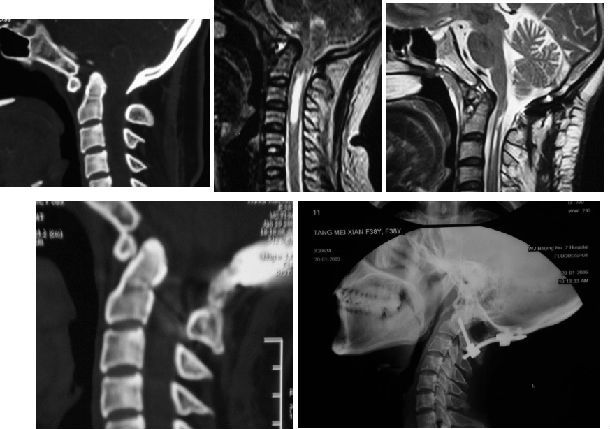

寰枢椎脱位枕颈融合术前、术后对比,可见寰枢椎脱位复位良好,延颈髓受压明显改善,脊髓空洞缩小。

手术前MRI显示:寰枢椎脱位(C1-C2间水平脱位10mm),脊髓明显受压变细。

手术前CT显示:寰枢椎脱位

手术后复查CT显示:寰枢椎脱位完全复位,脊髓受压明显改善,枕颈固定位置良好,局部植骨融合。